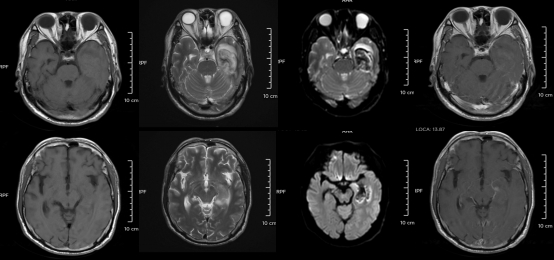

某單純皰疹病毒性腦炎患者的醫學影像。圖源:浙江大學醫學院附屬第二醫院

但如果拖延治療,甚至會引發腦炎,可能出現癲癇、肢體偏癱、尿潴留、認知功能障礙等嚴重后遺癥,恢復時間長達3-6個月,甚至影響終身。